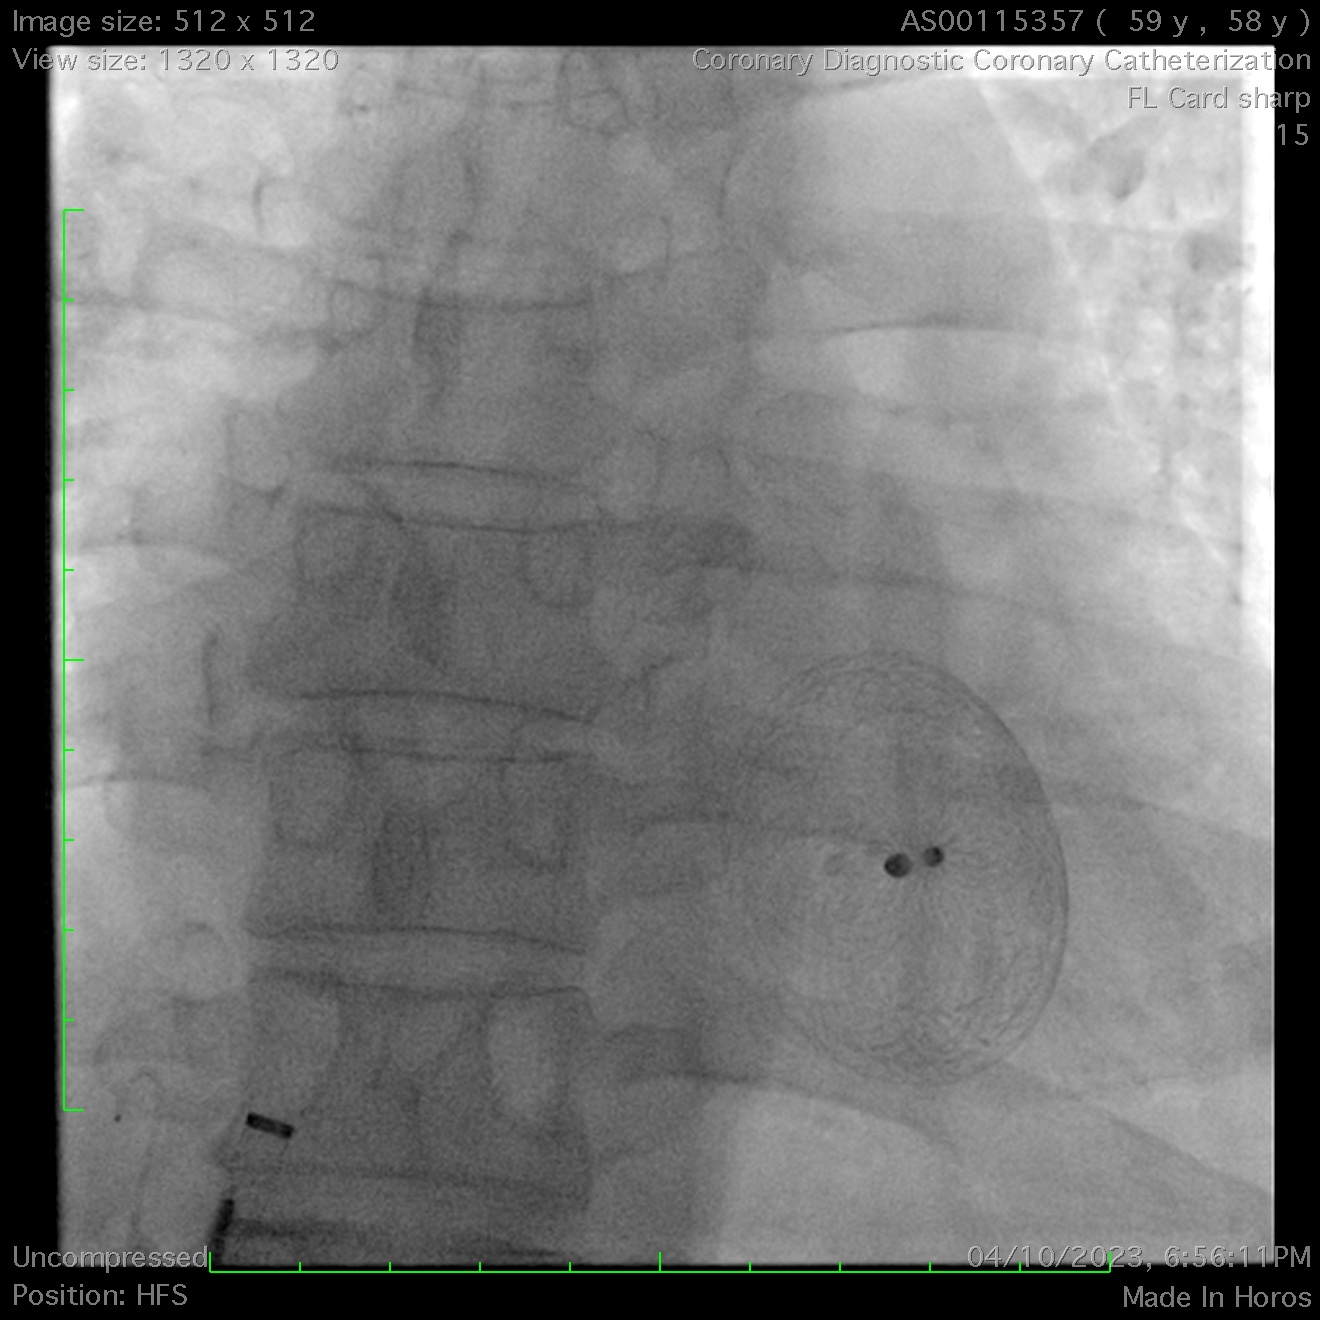

A 36mm ASD occluder was successfully deployed after confirming optimal position & stability. Unfortunately, post-release, the device embolized into the right ventricle. Agilis steerable catheters were inserted to bilateral femoral veins. Initial attempts to snare the occluder's hub with a single-loop snare proved challenging due to its high mobility within the right ventricle, even when stabilized with a steerable mapping catheter. A modified snare with a larger loop, made from a guiding catheter, coronary wire, and balloon, was employed but failed to capture the hub after multiple attempts.

Ultimately, a biopsy forceps was used to grasp the atrial disc and pull it into the inferior vena cava. This stabilized the occluder, enabling successful snaring of the left atrial disc’s hub into the left femoral sheath. Subsequently, a second snare was deployed from the right femoral sheath to capture the right atrial disc’s hub, allowing its sheathing & subsequent removal.